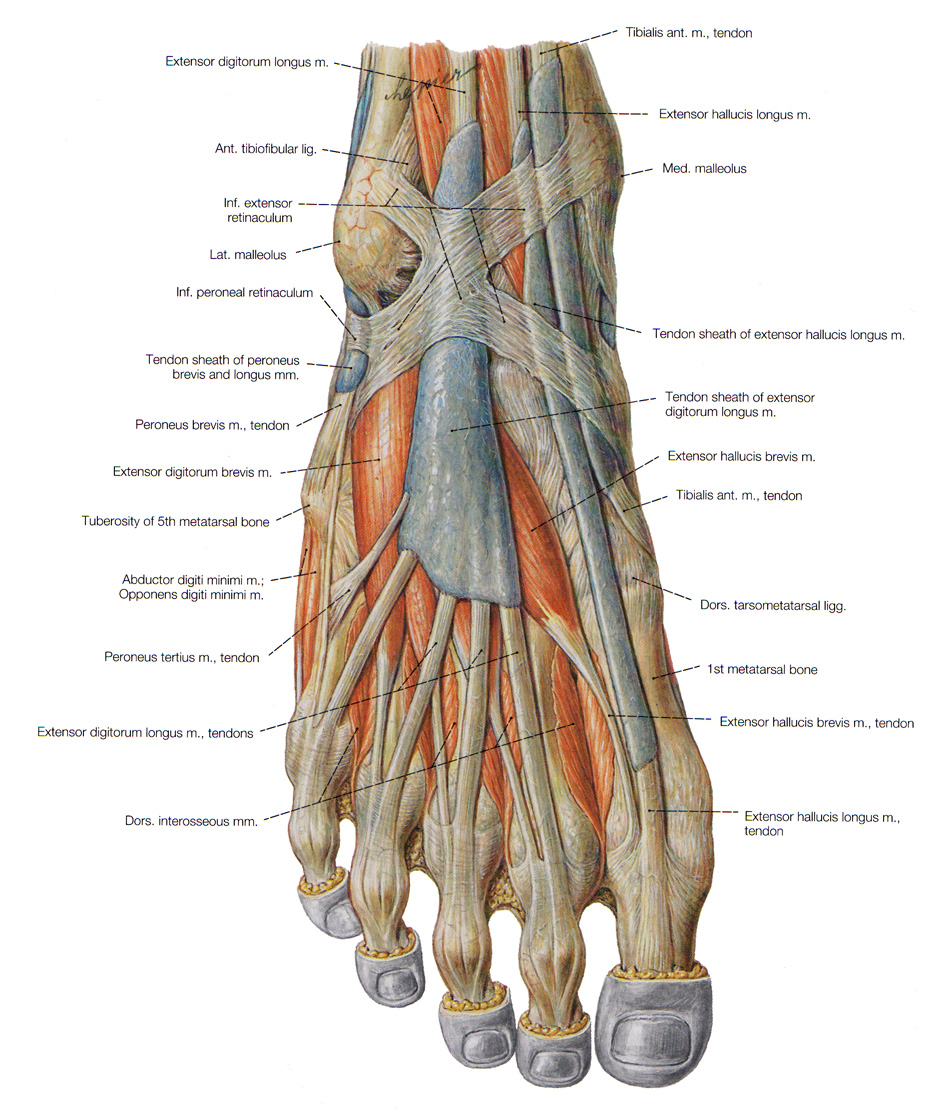

Анатомия подошвенной мышцы голени: подробное рассмотрение